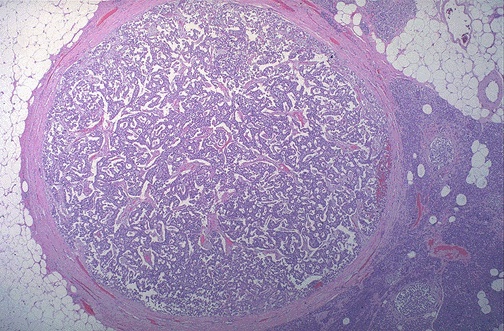

| This is a small islet cell tumor of the pancreas. It is well encapsulated and is an adenoma. Both benign and malignant islet cell tumors may, in some cases, function and secrete one or more hormones, including insulin, glucagon, gastrin, somatostatin, or even ACTH. |